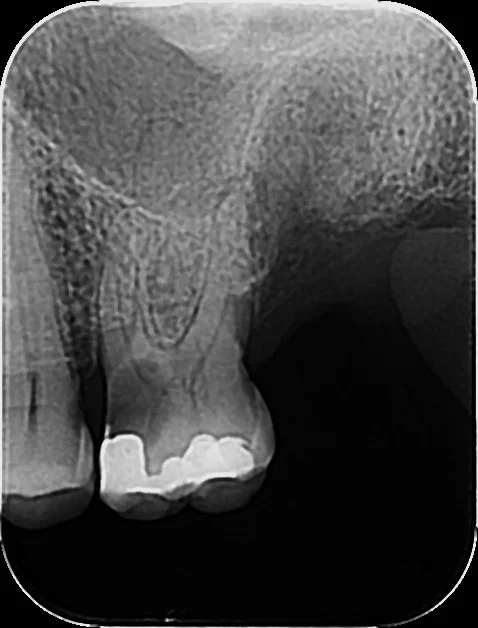

Digitalni zubni RTG – precizna dijagnostika uz minimalnu dozu zračenja Digitalni RTG omogućuje prikaz pojedinog zuba ili manjeg područja u vrlo visokoj rezoluciji. U Apex Dentalu koristimo moderne senzore koji daju iznimno jasnu sliku i zahtijevaju minimalnu izloženost zračenju. Prednosti digitalnog RTG-a: odmah gotova slika, minimalno zračenje, jasni detalji korijena i okolne kosti, idealno za endodontske zahvate, karijese i kontrole. APEX DENTAL ZADAR na Obali kneza Trpimira 21a kod Sfinge

#karijesdetektor

Da bi se svaki karijes otkrio na vrijeme

Pravodobnom snimkom zuba može se svaki karijes otkriti prije nego bude kasno i destrukcija zuba zbog karijesa dovede do gubitka samog zuba te potrebe za skupim zahvatima

RVG dijagnostika

Mala slika zuba,zanemarivo zračenje,otkrivanje karijesa na vrijeme i spašavanje zuba i zubnog živca,minimalni troškovi.

Neredoviti pregledi

Uništenje zuba zbog djelovanja karijesa, veliki porast troškova sanacije nastalog gubitka!